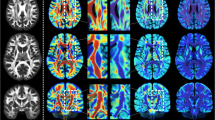

Fiber tracking is the most popular technique for creating white matter connectivity maps from diffusion tensor imaging (DTI). This approach requires a seeding process which is challenging because it is not clear how and where the seeds have to be placed. On the other hand, to enhance the interpretation of fiber maps, segmentation and clustering techniques are applied to organize fibers into anatomical structures. In this paper, we propose a new approach to automatically obtain bundles of fibers grouped into anatomical regions. This method applies an information-theoretic split-and-merge algorithm that considers fractional anisotropy and fiber orientation information to automatically segment white matter into volumes of interest (VOIs) of similar FA and eigenvector orientation. For each VOI, a number of planes and seeds is automatically placed in order to create the fiber bundles. The proposed approach avoids the need for the user to define seeding or selection regions. The whole process requires less than a minute and minimal user interaction. The agreement between the automated and manual approaches has been measured for 10 tracts in a DTI brain atlas and found to be almost perfect (kappa > 0.8) and substantial (kappa > 0.6). This method has also been evaluated on real DTI data considering 5 tracts. Agreement was substantial (kappa > 0.6) in most of the cases.